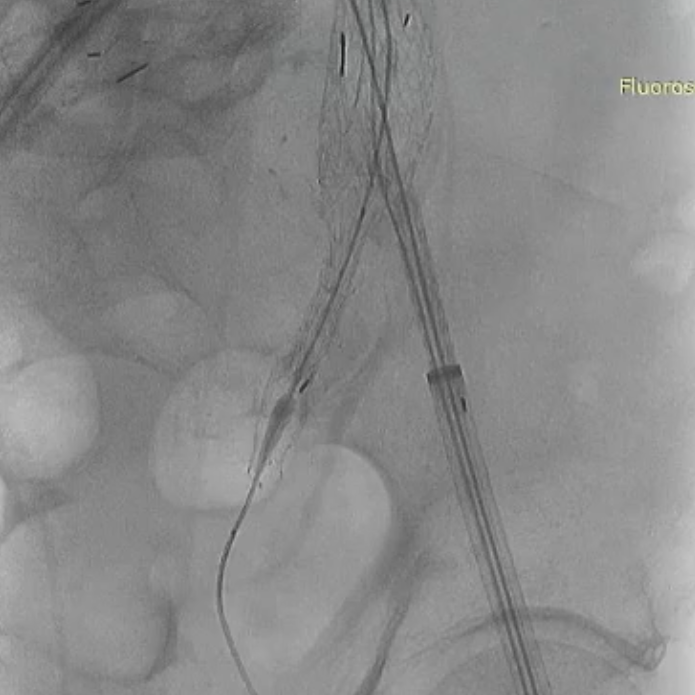

右侧髂内动脉重建完成后,建立对侧翻山通路,再次确认主体位置及左侧髂内动脉情况。左侧髂内超选困难,经反复确认导丝配合导管超选真腔,手推造影确认髂内情况后释放远端VB,释放左侧髂内分支HGB并确认通畅情况。最后按常规EVAR置入腹主动脉支架主体,超选入主体短腿内对接IBE主体释放桥接喇叭腿。

左侧髂内分支HGB释放

手推造影确认通畅情况

术后情况:造影提示动脉瘤完全隔绝,手术成功实现了保留双侧髂内动脉并隔绝动脉瘤的目标,患者病情得到有效控制。

术后造影